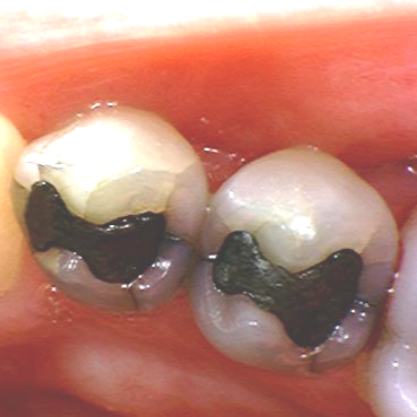

Usein varsinkin amalgaamilla paikatut hampaat ovat paikan alta halki jo pelkästään metallin ja lasimaisen hampaan erilaisten fysikaalisten ominaisuuksien takia. Siihen kun vielä lisätään vuosikymmenten pururasitus ja hampaan kulumisen aiheuttamien muodon ja voimien muutos, niin ei hampaiden halkeaminen kovinkaan suuri ihme ole.

TIESITKÖ TÄMÄN AMALGAAMISTA?

AMALGAAMILLA paikatut hampaat ovat paikan alta halki jo pelkästään metallin ja lasimaisen hampaan erilaisten fysikaalisten ominaisuuksien takia. Amalgaamia on käytetty hampaiden paikkauksessa lähes 200 vuotta.